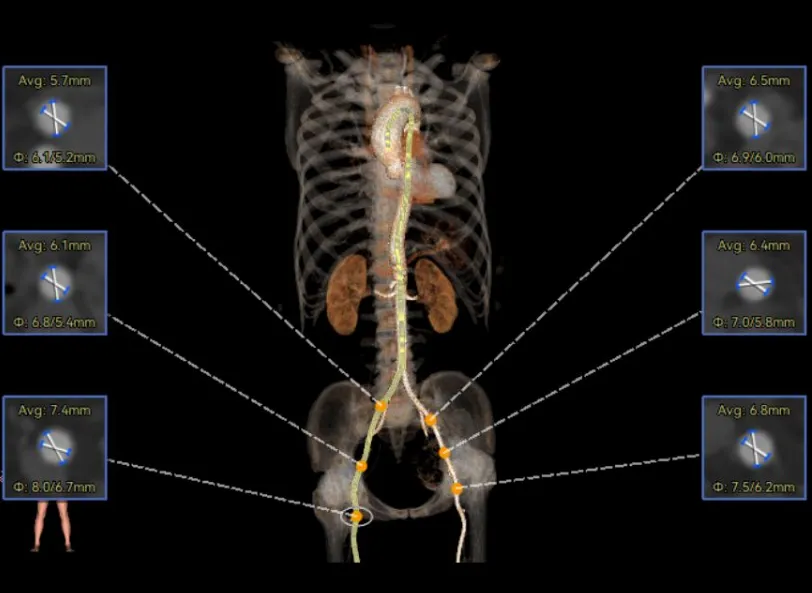

袁祖贻院长 西安交通大学第一附属医院 创新见证中国领跑,数据积累筑牢临床效果 韩克教授 西安交通大学第一附属医院 干瓣技术革新赋能特殊人群治疗,“量体裁衣”筑牢安全防线 患者病史 主诉与现病史:5年前因"血友病,血尿”就诊于当地医院,住院期间行心动超声提示主动脉瓣及二叶瓣畸形,无胸闷气短,无胸痛,咳嗽咳痰,无头晕,恶心呕吐等不适。未予以干预,后规律复查心超,3周前复查心超提示:主动脉瓣二瓣化畸形并重度狭窄,升主动脉内径明显增宽。 既往史:确诊血友病A型40年 术前超声提示:先天性主动脉瓣二叶式畸形,主动脉瓣中度狭窄,升主动脉增宽,左室舒张功能减低,EF73% 术前CT:Type0型二叶瓣,瓣叶增厚无钙化,主动脉瓣环径24.1mm,LVOT23.9mm;双侧冠脉开口高度可,窦部空间可,STJ、升主动脉内径可;预估冠脉低风险;主动脉水平夹角37.1°,主动脉弓角、弓距可;左室内径可;外周入路无明显迂曲,无钙化;双侧股动脉内径可,右侧股动脉低分叉。 手术策略 推荐右侧股动脉为主入路,左侧股动脉为辅入路。右股分叉上方1mm穿刺;仅舒张期时相,需根据球扩结果评估瓣膜尺寸,推荐使用18mm球囊进行预扩;预装AV26瓣膜。 手术过程 在右股动脉穿刺建立通路后,顺利送入大鞘。18mm球囊预扩后评估无腰无漏,后将Prostyle A® AV26瓣膜精准释放于目标位置,术后即刻造影显示无明显反流,无瓣周漏,平均跨瓣压差由术前的100mmHg降至2mmHg,患者血流动力学显著改善,术后超声证实瓣膜启闭良好。 主动脉根部造影 18球囊预扩 定位 稳定释放后脱钩 最终造影形态位置良好 外周血管造影,无血管并发症 术后超声显示无生物瓣位置固定瓣膜功能正常,无瓣周漏。 Prostyle A®预装干瓣——助力临床最优化解决方案 流入端桶状设计:流入端桶状的设计,锚定迅速,有效减少释放步骤,提升植入稳定性; 平衡的收腰设计:二叶瓣患者对瓣膜径向支撑力提出更高要求,Prostyle A®均衡的收腰设计可更好适应二叶瓣解剖,保证了EOA,有效降低了循环崩溃风险,提高瓣膜的耐久性; 预装干瓣 便捷顺安:金仕生物专利抗钙化技术运用纳米技术去除组织内的细胞碎片和磷脂,封闭游离醛基,从根本上阻断了瓣膜钙化的多项因素,显著提升了瓣膜的耐久性;同时,相比较传统戊二醛保存方式,干式存储最大限度的保留心包的亲水亲油平衡,还原组织天然曲柔性,进一步保障了瓣叶开合,保证长期耐久性。 专家简介 袁祖贻 西安交通大学第一附属医院(点击查看专家详细简历) 韩克 西安交通大学第一附属医院(点击查看专家详细简历) · END ·